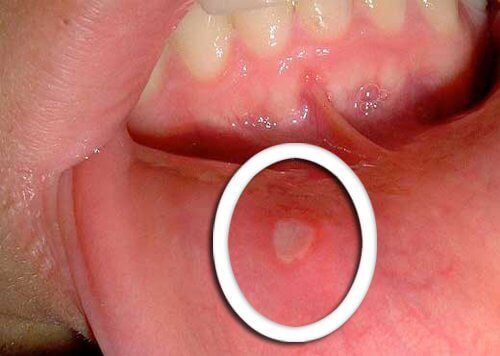

Физически промени в устата

- Най-ранният симптом на рак на гърлото са малките рани, които не се лекуват.

- Типично е да се появят червени или бели петна по езика, венците или на устните.

- Бъдете наясно с всякакви необичайни промени, които не се подобряват след няколко дни и отидете при вашия лекар.